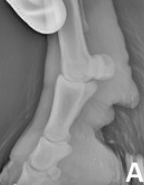

RX Images

In the 2013 Verena K. Affolter (U.C.Davis) study into CPL in Draft Horses there is a brief list of other potential diagnostics including lymphoscintigraphy and lymphangiogram. These procedures are expensive, invasive and unnecessary. Radiographs will show the extent of the folds but again are a surplus cost and show nothing that we can’t already see and feel, with regards to the CPL.